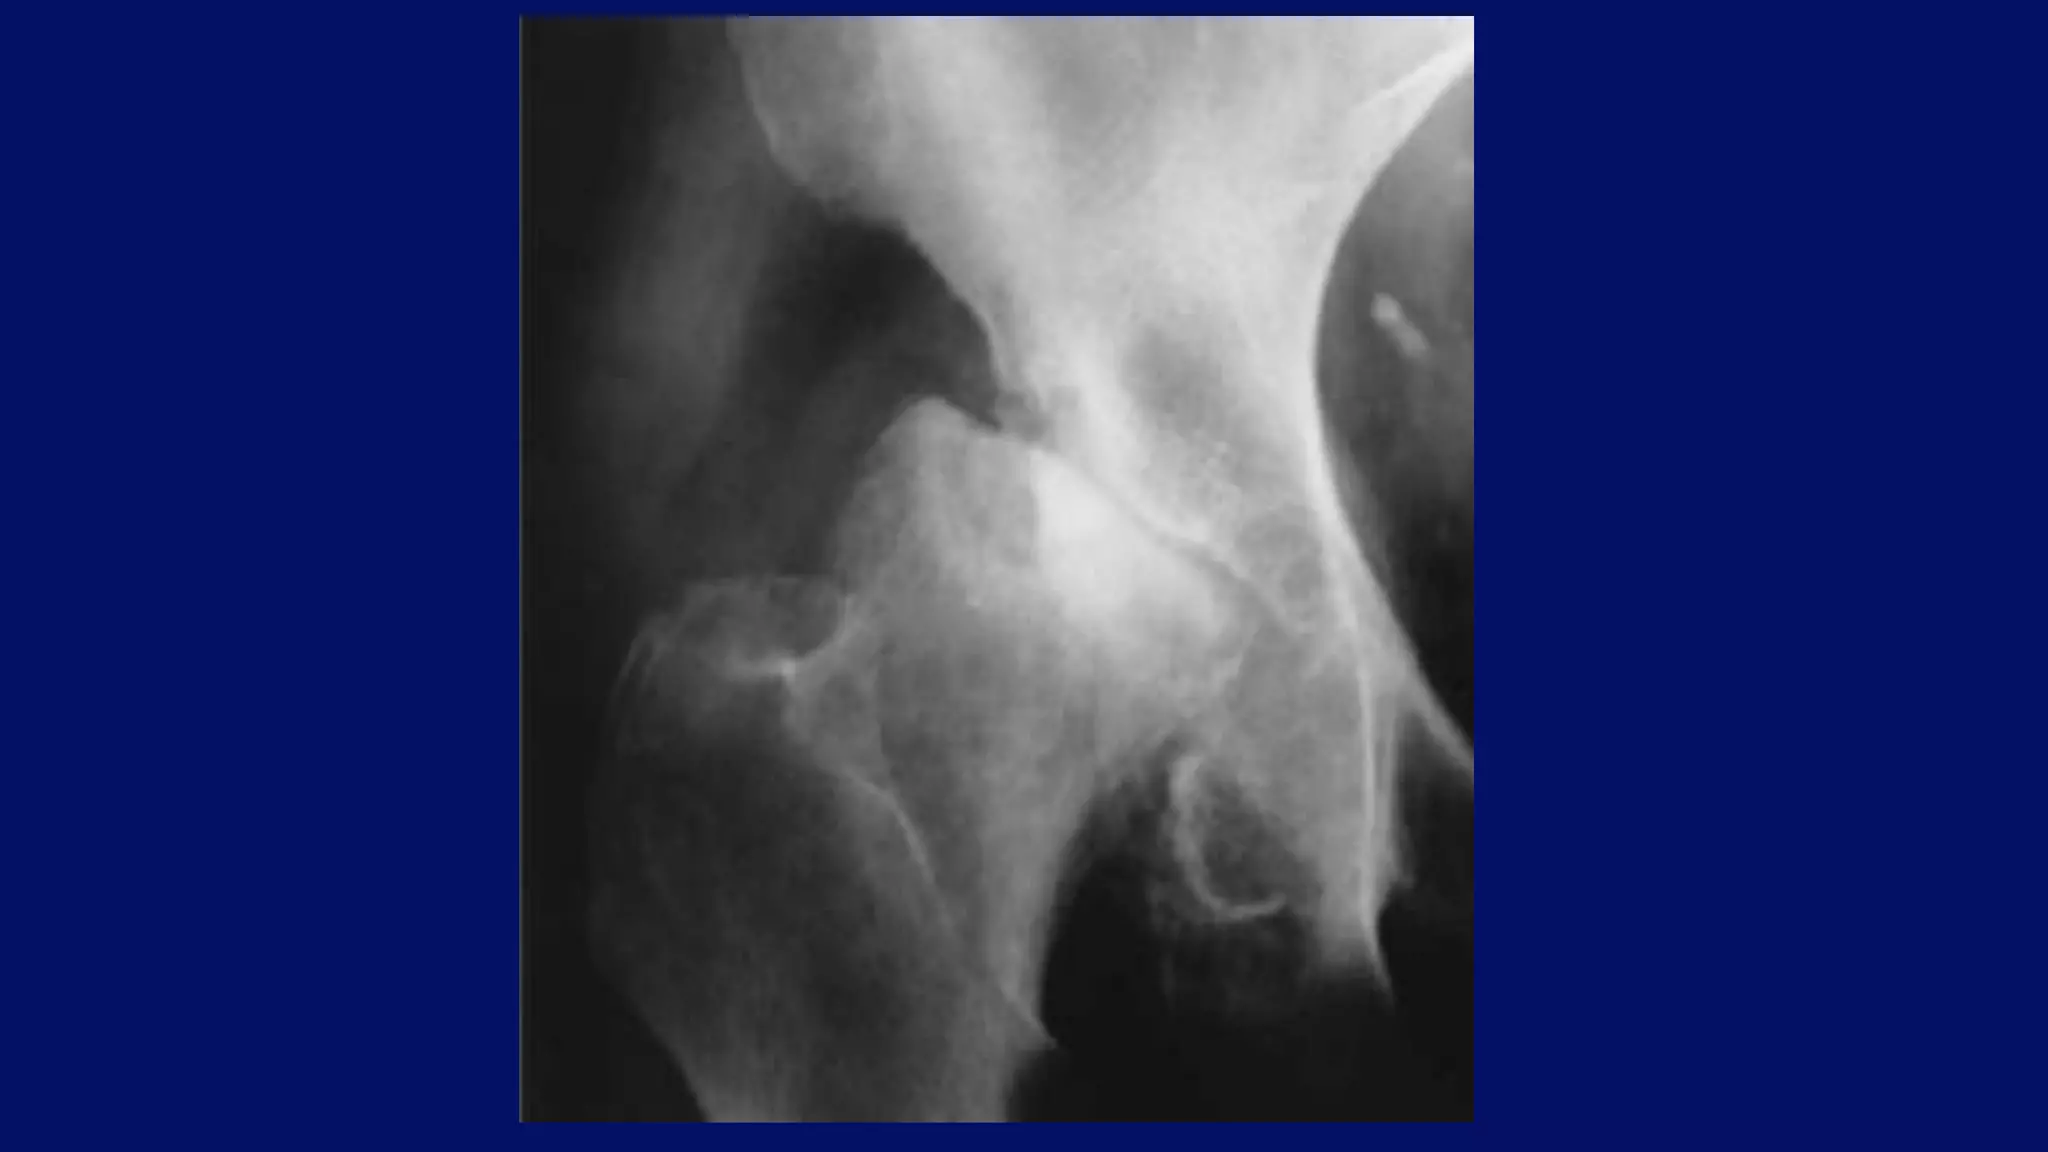

Medial migration of the femoral head

Postel coxarthropathy

(aka rapidly destructive arthrosis)

• occurs predominantly in women

• characterized by rapid chondrolysis

• no/very little reparative changes

• mimics Charcot joint or infectious arthritis

Right hip Postel Coxarthropathy

• #20 RDO has been defined by cartilage space narrowing of at least 2 mm per year whereas, in the usually seen form of OA, cartilage space narrowing of 0 to 0.8 mm is noted yearly. Rapid, marked bone loss from the femoral head and acetabulum occurs

• #21 Anteroposterior radiograph of the right hip of a 72-year-old man who had pain in the hip for 4 months shows the typical appearance of Postel coxarthropathy, which often mimics Charcot joint or infectious arthritis. Note the destruction of the articular portion of the femoral head, which is laterally subluxed. The same destructive process has led to widening of the acetabulum

• #22 Anteroposterior radiograph of the right hip of a 44-year-old man shows destructive changes of the femoral head and acetabulum.